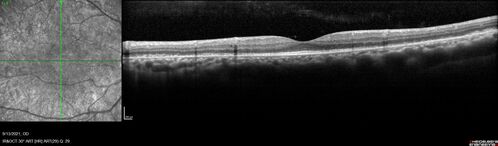

Ocular Lymphoma - Initially presented like auto-immune retinopathy

43 year old man: initial presentation - The vision in the left eye is blurry and opaque for about 2 weeks.  In the central of the vision, when he covers the right eye, in the center of the left eye there is a film with a light in the middle.  This has never happened before.  He has not been sick for the last few months.  A few weeks ago he saw waves on the floor when looking down but that has gone away.  Since the vision loss started the vision has not changed much.  The central vision is not getting better.

VA improved over 2 months to normal.  Then the patient had 2 more episodes of self-limited vision loss (no treatment).  Then 2 years later he presented with a diagnosis of CNS lymphoma and later developed subretinal deposits (last images)

lymphoma3_caflo_092021_47.jpg lymphoma3_caflo_092021_48.jpg lymphoma3_caflo_092021_49.jpg lymphoma3_caflo_092021_50.jpg lymphoma3_caflo_092021_46.jpg